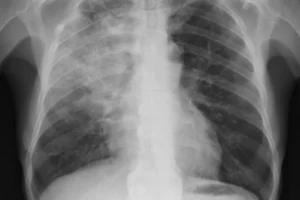

Принципы дифференциальной диагностики пневмонии

Пневмония имеет серьезные симптомы и может привести к серьезным осложнениям и даже смерти. По этой причине очень важно своевременно обратиться к врачу для постановки диагноза и постановки точного диагноза. Диагностика наиболее важна при лечении болезни, поскольку существует множество патогенов. Успех лечения зависит от результатов диагностики. Симптомы и критерии воспаления легких у взрослых Клиническая картина заболевания …